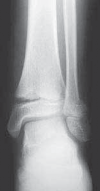

TECHNIQUES SALTER-HARRIS TYPE I AND II DISTAL TIBIA FRACTURES 1. A standard anterior approach for the SER fractures is used as described above.

2. For a medially gapped Salter Harris type II abduction injury, a medial approach is used (

TECH FIG 1

).

A B CTECH FIG 1•

Surgical approach to a medially gapped fracture.

A.

This AP radiograph demonstrates a medially gapped Salter-Harris type II abduction-type fracture.

B.

A medial approach is used to obtain open reduction of this fracture.

C.

This operative photograph highlights the periosteum interposed in the physeal fracture, which was extracted to obtain anatomic reduction and prevent medial gapping.